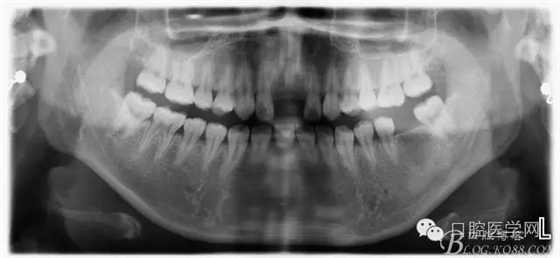

患者資料:XX女士,22歲。

主訴:前牙外傷多年。

現(xiàn)病史:前牙外傷兩年余,拔除后未處置,今來(lái)診治。

檢查:11.21缺失,笑線高,牙齦較薄,齦乳頭地坪,牙槽骨較飽滿;12.22隱裂,冷熱(一),叩診(一)

診斷:牙齒缺失,牙隱裂。

術(shù)前:該患者因曾受過(guò)外傷,造成兩顆中切齒缺失,來(lái)院診治。